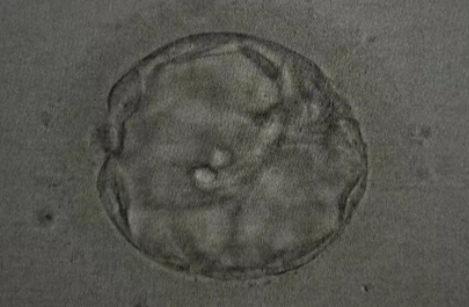

• 养囊成功:2颗

▲ Z女士的养囊报告

PGT-A染色体筛查结果

• 2 枚囊胚送检,2 枚过筛 - 适合移植

▲ Z女士的胚胎筛查报告